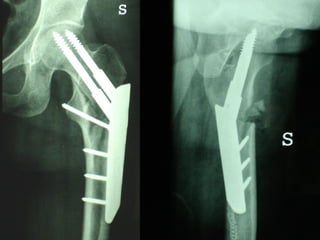

La placca a compressione percutanea (PC.C.P.) di Gotfried è un mezzo di sintesi studiato per assicurare un “impattamento controllato” delle fratture pertrocanteriche grazie alle due viti telescopiche prossimali che garantiscono una ottima stabilità rotazionale

Con la placca di Gotfried non si è mai riscontrato un danno iatrogeno del muro laterale e nessun collasso della frattura.Ciò è dovuto al fatto che i fori per l’applicazione delle due viti prossimali sono di piccolo diametro (9 mm) rispetto ai 16-32 mm necessari per introdurre la vite cefalica di un chiodo endomidollare o di una vite-placca a compressione.

Dal Gennaio 2005 ad Agosto 2006 110  placche di Gotfried Età media  : 78 anni (range 29-94) Tempo chirurgico: 30 minuti (range 12-45) IMMEDIATA CONCESSIONE DEL CARICO

3  INSUCCESSI

CONCLUSIONI Perché non mettere un chiodo?  Senz’altro se il muro  laterale è fratturato  così come il punto di introduzione della  vite cefalica,perché la tecnica è più semplice

… ma  se il muro laterale è integro , la sintesi con la placca di Gotfried è  migliore e se  applicata con la  necessaria perizia tecnica garantisce  ottimi risultati.